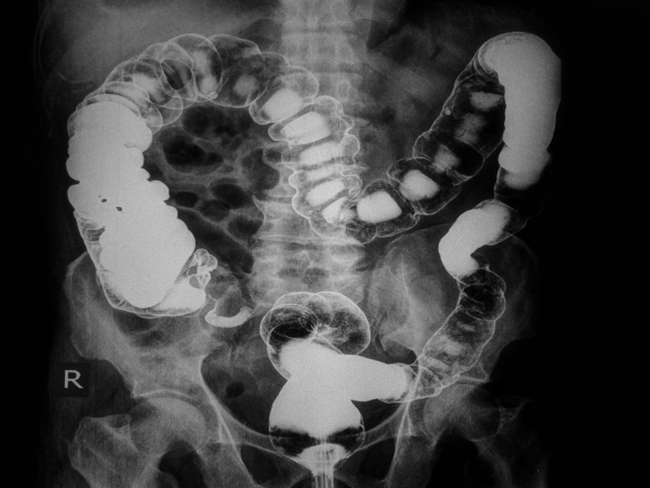

10. Sàng lọc nguy cơ ung thư: Sàng lọc ung thư trực tràng có thể phát hiện sớm được polyp, tiền thân của khối u sớm, thậm chí nhiều năm trước khi chúng phát triển thành ung thư. Các bác sĩ sau đó có thể loại bỏ ung thư trực tràng bằng cách loại bỏ các polyp. |